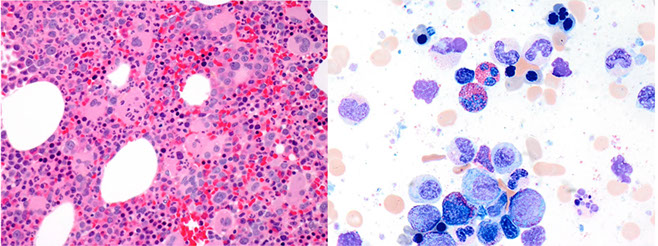

Low power morphologic abnormalities in MDS

BM findings

Usually hypercellular marrow for age with erythroid hyperplasia, but may see normocellular or hypocellular marrow

Generally increased number of blasts

Generally trilineage dysplasia (dyshematopoiesis)

- Abnormal localization of immature myeloid precursors (ALIP)

Dysmegakaryopoiesis

Dyserythropoiesis

Dysgranulopoisis

Dysmegakaryopoisis

Meg dysplasia

Granulocytic dysplasia

Erythroid dysplasia [3].

Refractory Anemia (BM)